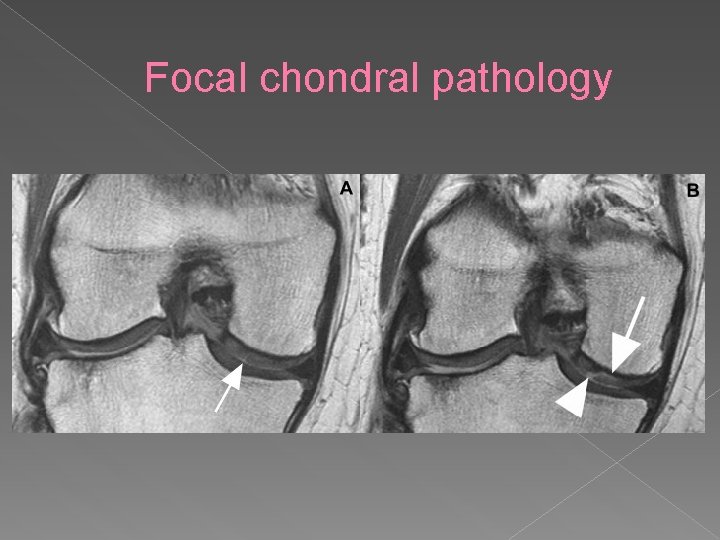

Focal chondral pathology